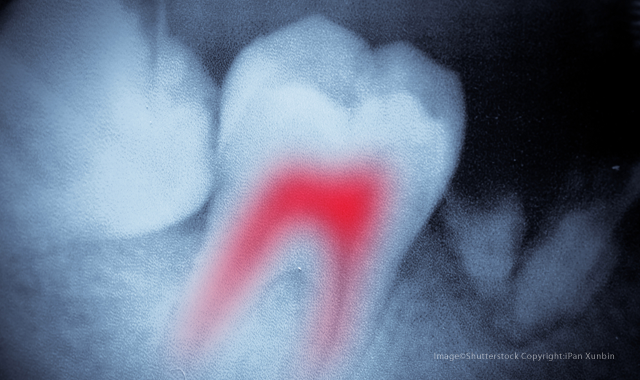

The new method of detecting bacteria during root canal treatments could eliminate secondary infections and the need for follow-up visits.

Since approximately a quarter of root canals fail over time due to secondary infections, the ability to detect potentially hazardous leftover bacteria at the time of treatment could be extremely beneficial. It could also cut down on the number of visits, as most procedures currently require one or two secondary visits to the dentist. The new device, called SafeRoot, was created to detect any remaining bacteria at the completion of root canal treatment to reduce the need for reintervention or extraction

Created by Mannooci and group of fellow researchers at King’s College London, SafeRoot detects residual live bacteria in the root canal area using Calcein acetoxymethyl, a florescent dye, and fluorescence microscopy/spectroscopy. In clinical trials, the process, which is performed during the root canal treatment and uses standard sterile endodontic paper points for sampling, successfully detected bacteria after three minutes of testing.